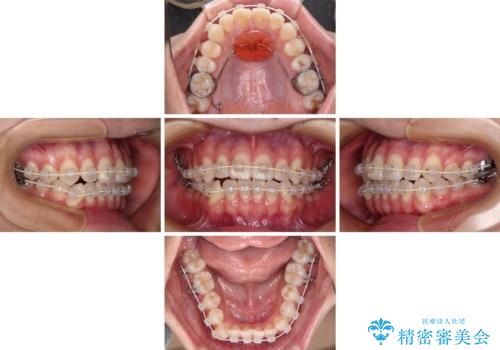

- 前歯のデコボコと奥歯の咬み合わせを気にして来院された患者様です。

右側の奥歯は、上が外側に転位した鋏状咬合を呈しており、前歯のデコボコ改善と並行して咬み合わせを改善していく必要がありました。

装置はワイヤー装置でもインビザラインのマウスピースでもどちらでも適用でしたが、自己管理の煩わしさを嫌い、ワイヤー矯正にて治療を行うこととしました。

ワイヤー矯正を選択されたため、鋏状咬合を確実に改善するために補助装置を併用することとしました。